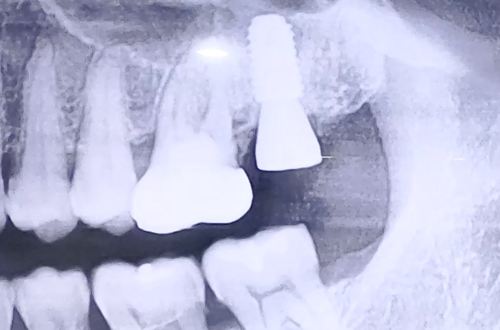

AFTER

더 튼튼하고 효율적인 임플란트 치료를 위해 CT 촬영으로 염증의 위치를 정확하게 파악하는 정밀검사를 더하였고, 염증을 제거해준 뒤 비교적 튼튼히 남아있는 잇몸뼈 쪽으로 식립 후 뼈이식으로 단단히 해 드렸습니다.

꼼꼼한 검진의 중요성을 일깨울 수 있었던 케이스로, 최종 보철까지 마무리되면 다시 진료일지로 찾아뵙겠습니다. ^^